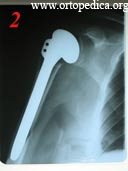

1. Больная М. Оскольчатый перелом головки правой плечевой кости со смещением